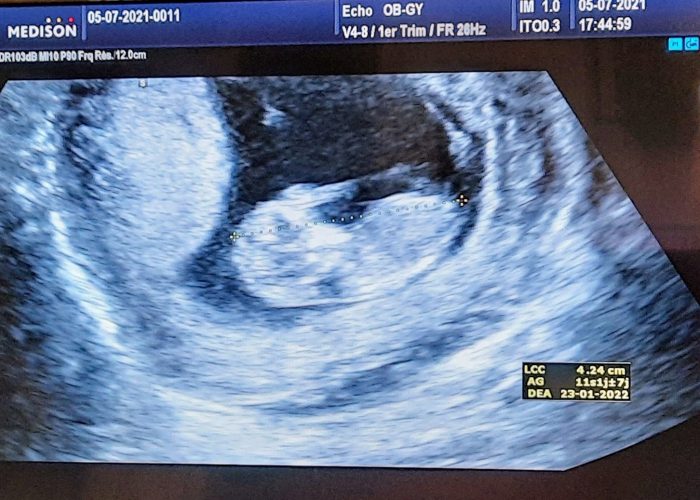

My (second) Pregnancy Diary: First Trimester Anxiety and Discomforts

My Pregnancy: Nuisances and the Better Highlights